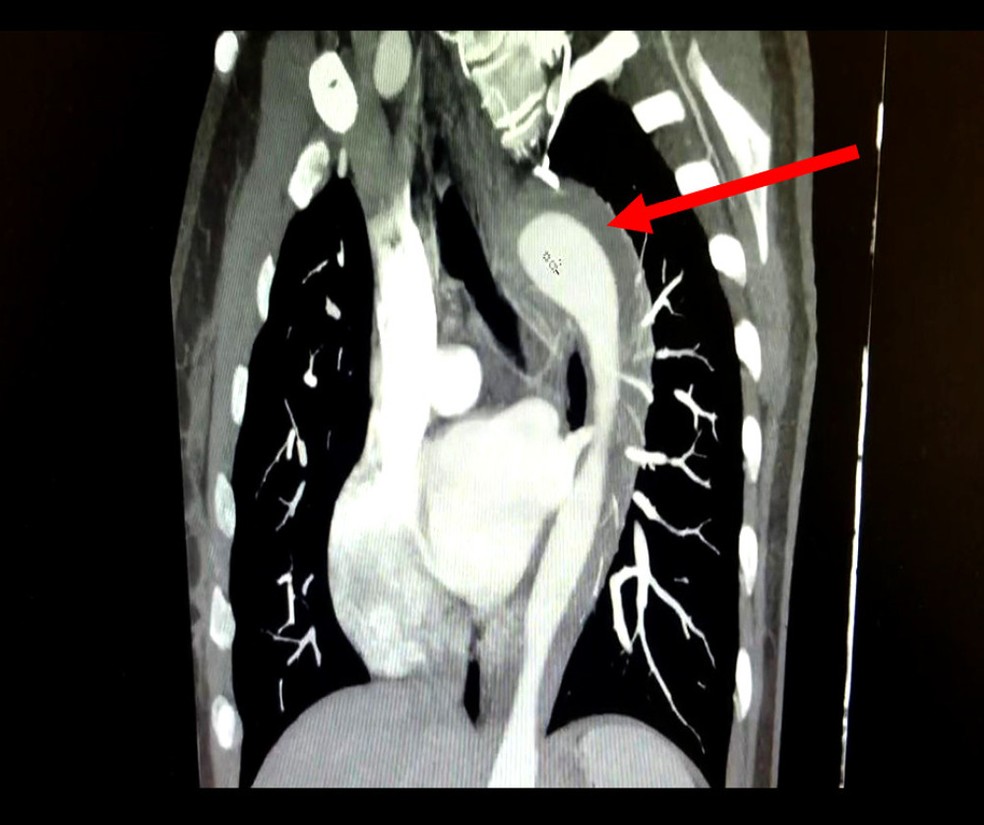

Segundo os médicos que atenderam o caso, a paciente tinha hipertensão não tratada há um ano e tabagismo há 17 anos. Para entender o que aconteceu, ela passou por exames de imagem que indicaram hematoma intramural na aorta.

🫀O hematoma intramural na aorta é uma condição grave que envolve o sangramento na parede da aorta. O quadro é considerado uma Síndrome Aórtica Aguda (SAA) e, se não tratado adequadamente, pode evoluir para aneurisma ou ruptura aórtica total, com risco de vida ao paciente.